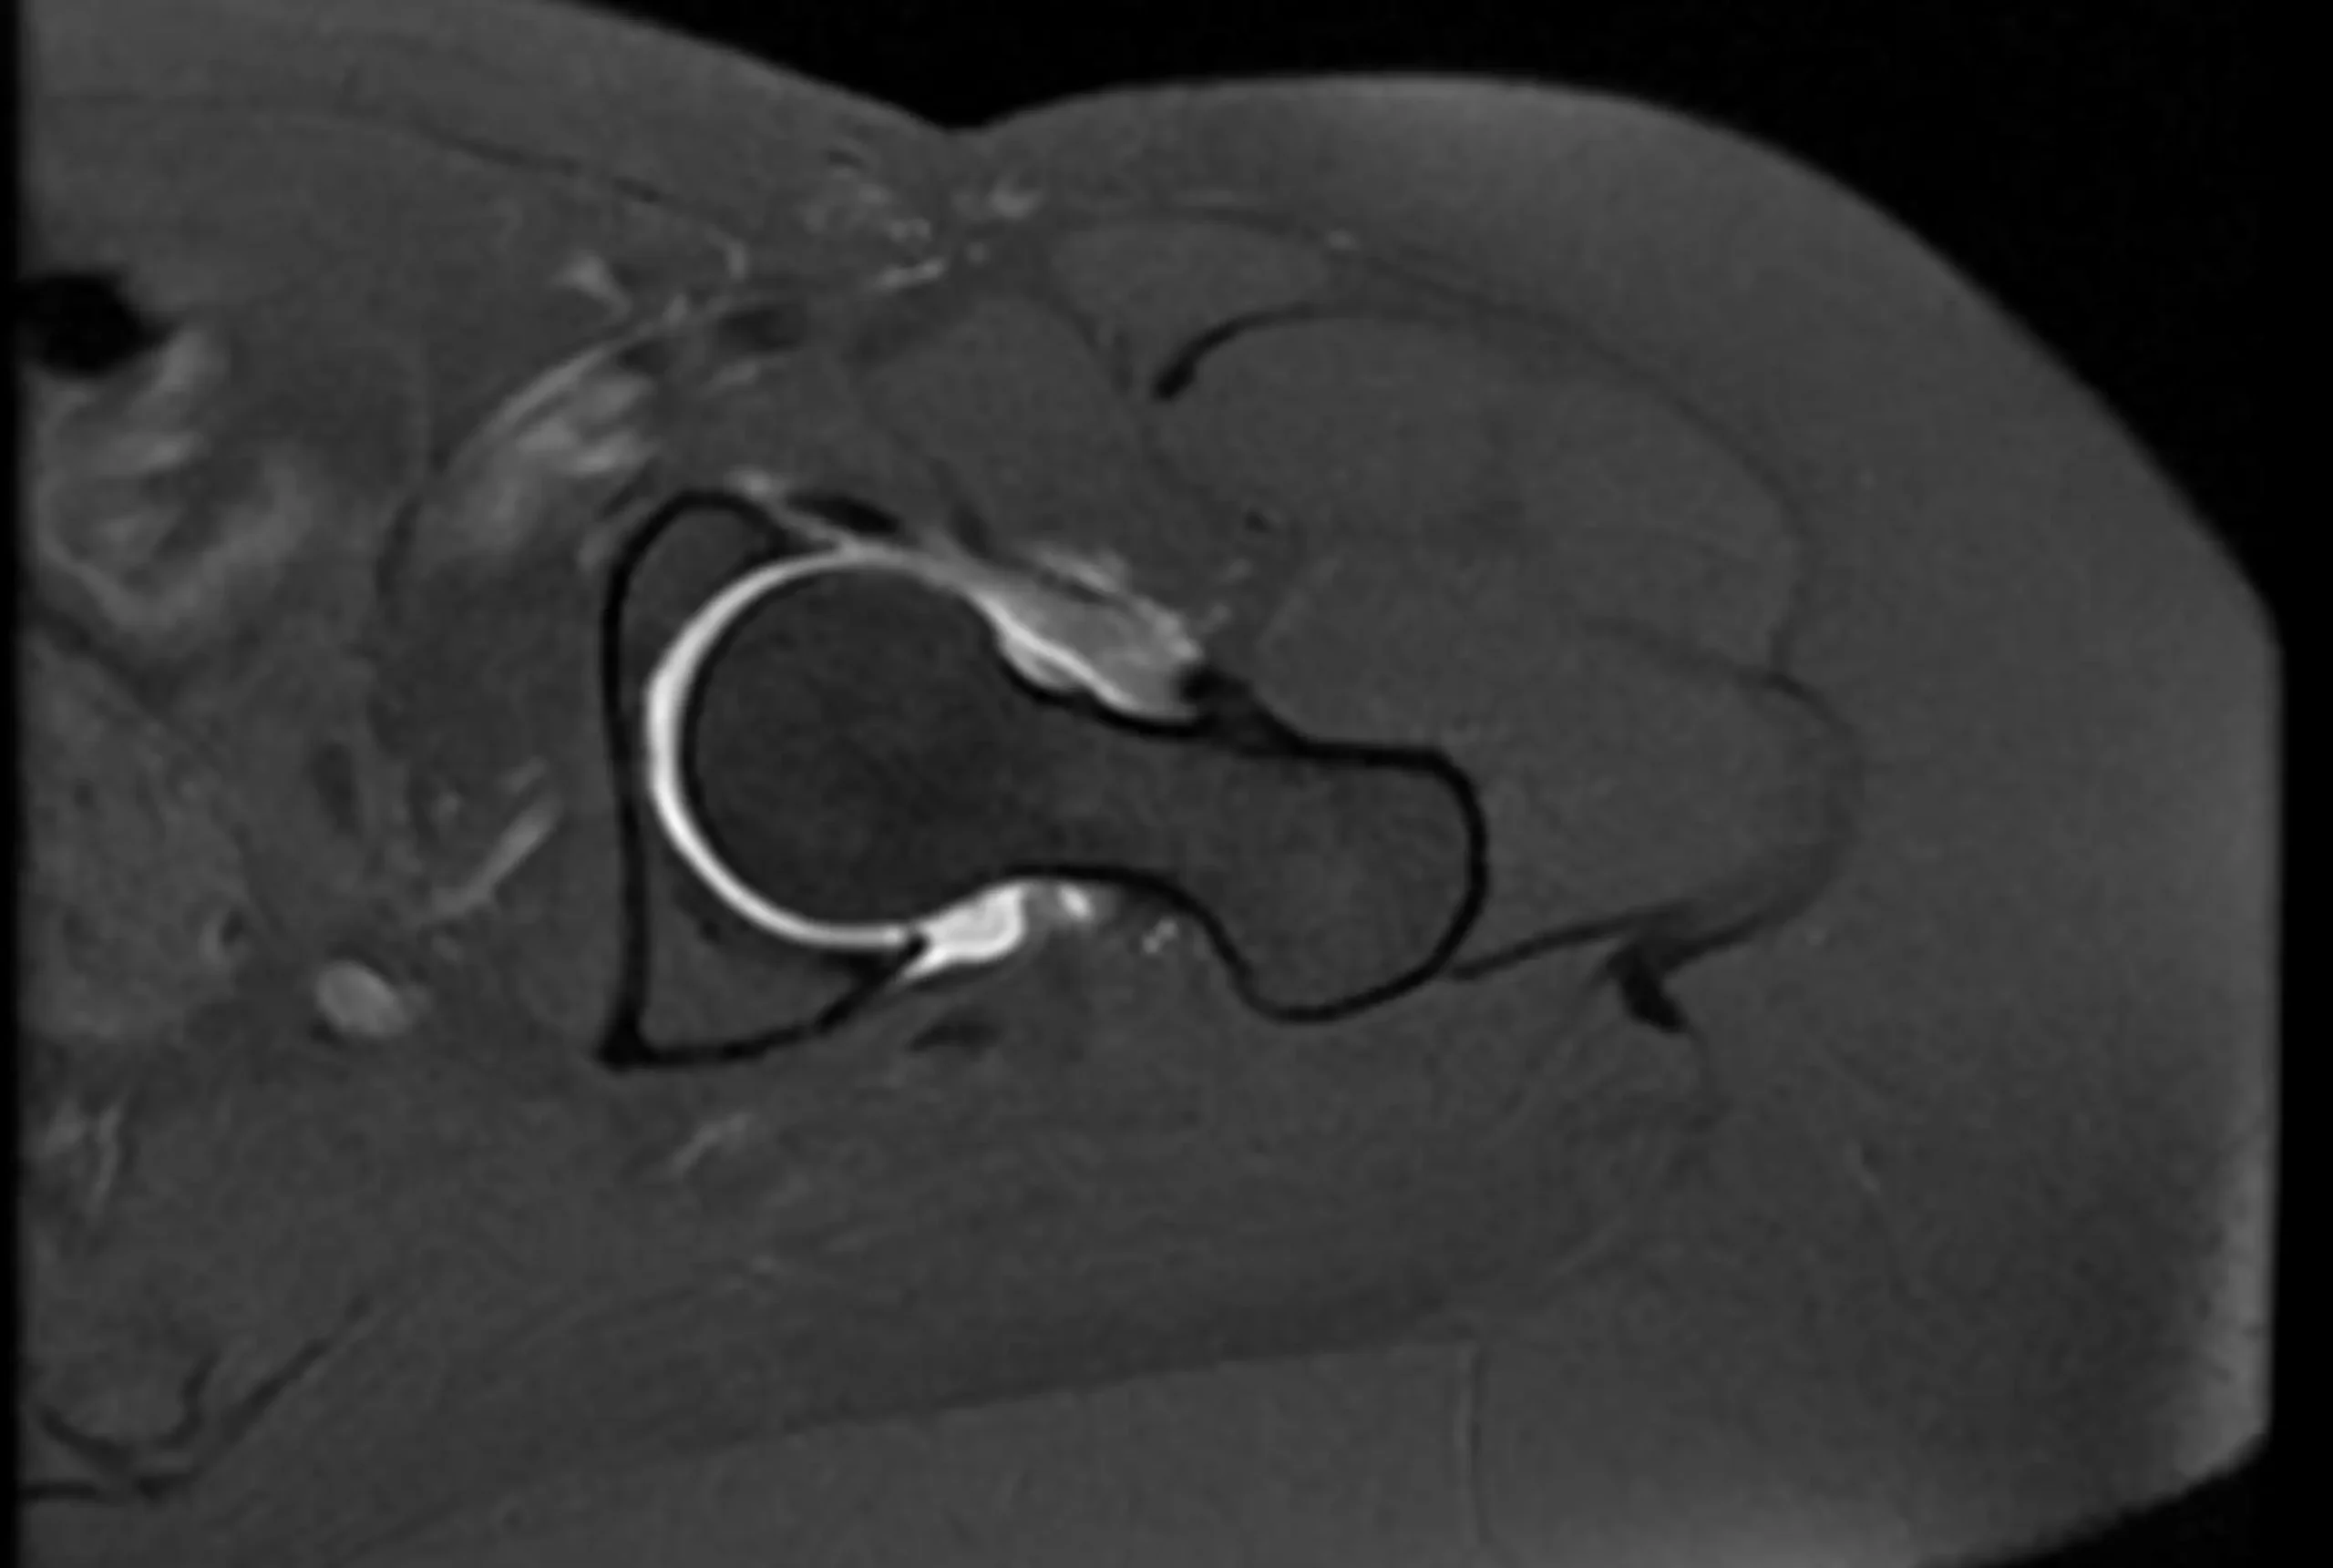

Es un estudio especializado de resonancia magnética donde el medio de contraste en vez de ser inyectado por vía intravenosa se inyecta directamente en la articulación para una mejor visualización de las estructuras articulares y mayor precisión diagnóstica en casos especiales, a estos estudios se les llama Artro-resonancia magnética y se utiliza principalmente en el estudio de la articulación de la cadera y articulación del hombro.